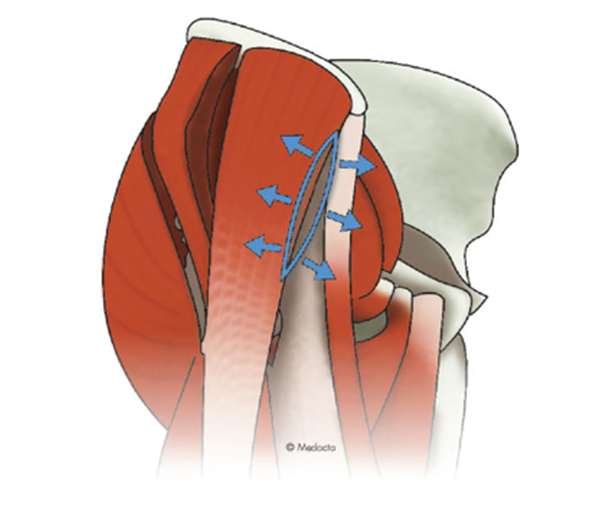

前方系アプローチの場合は、筋肉や腱を切らずに、筋肉の間から侵入するため、“筋・腱温存手術”と言われ、体へのダメージが少なく、脱臼のリスクも少ないのが特長です。組織の大部分を温存できるので、出血や痛みが少なく、術後の回復が非常に早いのも大きなメリットです。

どちらも、筋肉や腱を切らないため、ダメージの少ない『最小侵襲手術』です。その中でも、前方アプローチ(DAA、AMIS)は、筋間アプローチでもあり、神経間アプローチでもあります。より分ける筋肉の間を交通する神経がないため、神経へのダメージも防ぐことが可能です。

MIS(最小侵襲手術)とはできるだけ正常組織を傷めずに手術をすることで、術後の早期リハビリや回復を目指す方法です。当院ではMISである前方系アプローチのなかでも特に侵襲が少ないといわれるAMIS(前方最小侵襲手術)という手技で人工股関節手術を行っています。AMISは、専用の牽引手術台を使用して行う前方アプローチで筋肉をまったく切離せず、さらに関節周囲の軟部組織も極力温存する特殊な方法です。関節を覆う関節包さえも切除せず温存することで、股関節はより安定し、さらに脱臼しにくくなると考えています。フランスで報告されて以来、世界的にも認められた非常に有用な手技ですが、誰にでも行える手術ではなく、ライセンス認定を受けた医師のみが行える手術手技です。体へのダメージや痛みも少なく、術後の早期回復や、高い脱臼抵抗性(脱臼のしずらさ)が大きなメリットです。*変形の程度や術者によりアプローチが異なる場合があります。